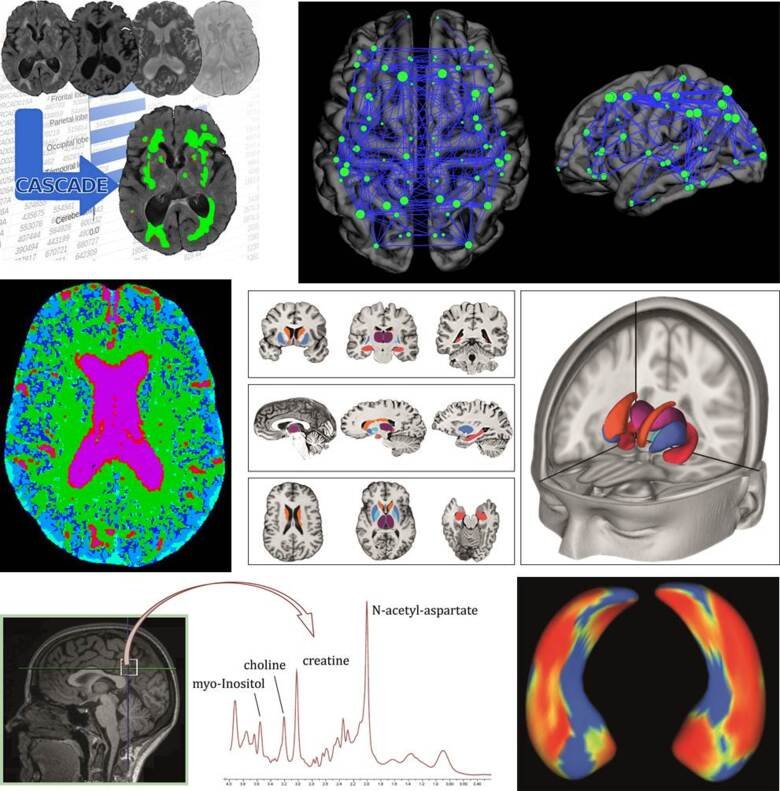

Structural and functional neuroimaging play an important role in understanding the underlying mechanisms of different dementia disorders, potentially contributing to their management and diagnosis. We have a strong focus in different magnetic resonance imaging (MRI) techniques, such as structural MRI, magnetic resonance spectroscopy (MRS), functional MRI, diffusion tensor imaging (DTI), arterial spin labeling (ASL) and susceptibility weighted imaging (SWI). In addition to MRI, we work with other imaging modalities, such as positron emission tomography (PET) and computed tomography (CT).

We work with advanced tools to analysis neuroimaging data such as multivariate methods, machine learning and graph theory. Currently, a large part of the research within the group is focused on unraveling the heterogeneity in AD and to understand the substantial overlap between the different disorders. We believe it is important to work with the latest neuroimaging techniques to obtain a better understanding of the underlying mechanisms of the different diseases, to improve early diagnosis and differential diagnosis.